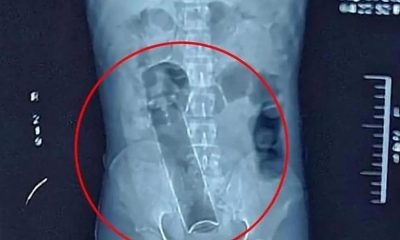

Paciente descobre tesoura cirúrgica dentro do corpo sete meses após operação

Uma mulher de 53 anos denunciou um cirurgião plástico às autoridades italianas após descobrir uma tesoura cirúrgica esquecida dentro do...